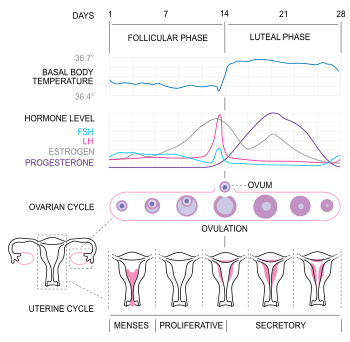

In humans, ovulation occurs about midway through the menstrual cycle, after the follicular phase. The few days surrounding ovulation (from approximately days 10 to 18 of a 28-day cycle), constitute the most fertile phase.[3][4][5][6] The time from the beginning of the last menstrual period (LMP) until ovulation is, on average, 14.6[7] days, but with substantial variation between females and between cycles in any single female, with an overall 95% prediction interval of 8.2 to 20.5[7] days.

The process of ovulation is controlled by the hypothalamus of the brain and through the release of hormones secreted in the anterior lobe of the pituitary gland, luteinizing hormone (LH) and follicle-stimulating hormone (FSH).[8] In the pre-ovulatory phase of the menstrual cycle, the ovarian follicle will undergo a series of transformations called cumulus expansion, which is stimulated by FSH. After this is done, a hole called the stigma will form in the follicle, and the secondary oocyte will leave the follicle through this hole. Ovulation is triggered by a spike in the amount of FSH and LH released from the pituitary gland. During the luteal (post-ovulatory) phase, the secondary oocyte will travel through the fallopian tubes toward the uterus. If fertilized by a sperm, the fertilized secondary oocyte or ovum may implant there 6–12 days later.[9]

The follicular phase (or proliferative phase) is the phase of the menstrual cycle during which the ovarian follicles mature. The follicular phase lasts from the beginning of menstruation to the start of ovulation.[10][11]

Estrogen levels peak towards the end of the follicular phase. This causes a surge in levels of luteinizing hormone (LH) and follicle-stimulating hormone (FSH). This lasts from 24 to 36 hours, and results in the rupture of the ovarian follicles, causing the oocyte to be released from the ovary via the oviduct.[12]

The follicle proper has met the end of its lifespan. Without the oocyte, the follicle folds inward on itself, transforming into the corpus luteum (pl. corpora lutea), a steroidogenic cluster of cells that produces estrogen and progesterone. These hormones induce the endometrial glands to begin production of the proliferative endometrium and later into secretory endometrium, the site of embryonic growth if implantation occurs. The action of progesterone increases basal body temperature by one-quarter to one-half degree Celsius (one-half to one degree Fahrenheit). The corpus luteum continues this paracrine action for the remainder of the menstrual cycle, maintaining the endometrium, before disintegrating into scar tissue during menses.[14]

Females near ovulation experience changes in the cervix, in mucus produced by the cervix, and in their basal body temperature. Furthermore, many females experience secondary fertility signs including Mittelschmerz (pain associated with ovulation) and a heightened sense of smell, and can sense the precise moment of ovulation.[15][16]

Symptoms related to the onset of ovulation, the moment of ovulation and the body's process of beginning and ending the menstrual cycle vary in intensity with each female but are fundamentally the same. The charting of such symptoms — primarily basal body temperature, Mittelschmerz and cervical position — is referred to as the sympto-thermal method of fertility awareness, which allow auto-diagnosis by a female of her state of ovulation. Once training has been given by a suitable authority, fertility charts can be completed on a cycle-by-cycle basis to show ovulation. This gives the possibility of using the data to predict fertility for natural contraception and pregnancy planning.